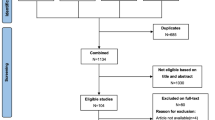

This study was carried out between December 2015 and June 2017. Cases who were scheduled for biphasic pancreatic protocol MDCT examination with a presumed diagnosis of pancreatic tumor were eligible for the study. Pancreatic parenchymal phase images were evaluated on-console by a radiologist for the presence of a tumor or tumor suspicion and the decision to perform pCT was given subsequently. 89 patients with an overt pancreatic tumor or with secondary findings indicative of tumor such as abnormal contour of the pancreas, sudden termination of the choledochal and/or pancreatic duct, and mild to moderate atrophy of the parenchyma distal to the lesion on CECT underwent pCT. Patients with a definite histopathological diagnosis of PDAC or MFCP by either surgery (n = 44), percutaneous biopsy (n = 12), or endoscopic ultrasound (EUS)-guided fine needle aspiration cytology (FNAC) (n = 17) were included in the study. Exclusion criteria were presence of any renal function disorder, a known allergy to contrast medium (CM), history of pancreatic surgery or chemotherapy, absence of a pathological diagnosis or diagnoses other than PDAC or MFCP like endocrine tumors and other cystic and solid masses, and presence of severe distal parenchymal atrophy. The inclusion and exclusion criteria are shown in flow diagram (Fig. 1).

Seventy-three cases (34 woman–39 men; mean age 68 ± 0.8 years; range, 27–90) were finally included in the study. Sixty-one cases received a pathological diagnosis of PDAC (12 on percutaneous biopsy, 17 on EUS-guided FNAC, and 44 via surgery). Of 12 MFCP cases, 8 were diagnosed by EUS-guided FNAC and 4 were diagnosed by percutaneous biopsy. MFCP cases have been followed for 15–24 months, and none has been developed malignancy. A flow diagram on pathological diagnosis distribution and MDCT scanning features in cases where pCT was performed is presented in Fig. 1.